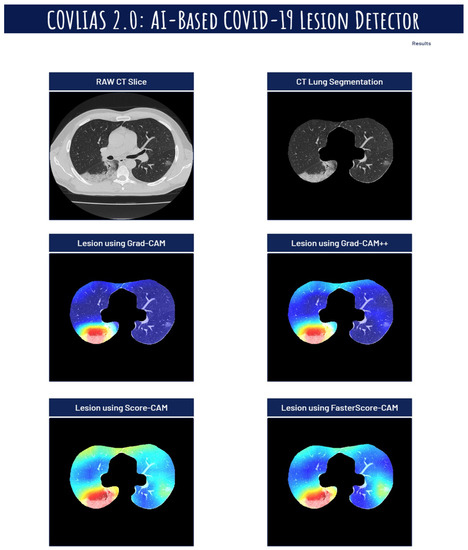

Visual Results Representing Lesion Using the Four CAM Techniques